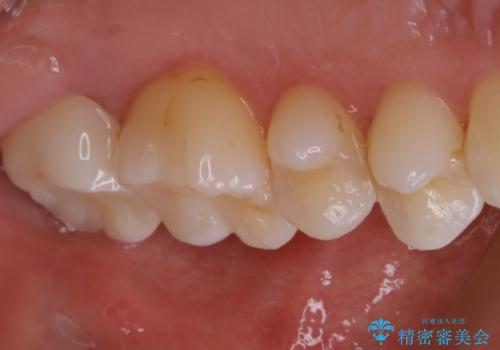

保険治療の白い歯が割れた。

- 4~5年前に保険治療で入れた白い被せ物が割れたと患者様は来院されました。

土台となる自身の歯は虫歯にはなっていませんでした。保険で入れる白い被せ物は壊れやすく劣化するものです。セラミックとの違いを説明した上で、患者様はセラミックを希望されたため、オールセラミッククラウンをかぶせることとなりました。

今回の患者様の歯の色調について。縞模様が入った3段階の色調でした。オールセラミックのスタンダードの場合技工士さんの立会いがないため、言葉では技工士さんに伝えにくかったり色の再現性が難しい時に歯の色味を伝えるための写真画像を技工所に送ります。